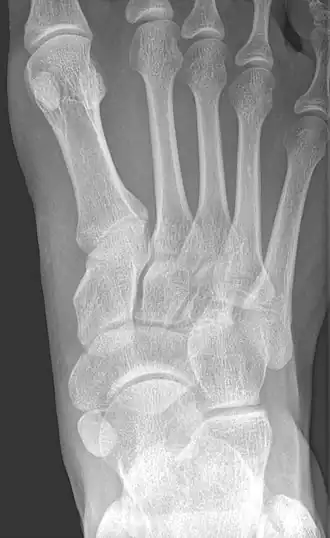

Radiographie du pied montrant un os naviculaire accessoire

Un os naviculaire accessoire est un os accessoire du pied qui se développe parfois anormalement devant la cheville vers l'intérieur du pied. Cet os peut être présent dans environ 2 à 14 % de la population générale et est généralement asymptomatique[1],[2],[3]. Lorsqu'il est symptomatique, une intervention chirurgicale peut être nécessaire.

L'os naviculaire accessoire peut provoquer un étirement continu et une tension sur le tendon postérieur tibial qui peut évoluer vers une douleur chronique invalidante et peut provoquer une rupture du tendon ou une déformation secondaire du pied plat, lorsque cela se produit, cette condition est communément appelée syndrome naviculaire accessoire[4]. D'autres conditions qui imitent étroitement les symptômes d'un os naviculaire accessoire incluent fasciite plantaire, oignons et épine calcanéenne.

Les radiographies sont généralement commandées pour confirmer le diagnostic. S'il y a une douleur ou une inflammation en cours, une IRM ou d'autres tests d'imagerie avancés peuvent être utilisés pour évaluer davantage la condition.

Images radiologiques